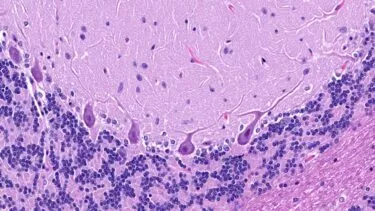

Forskere opdager 3.300 nye typer celler i menneskehjernen

Hjernen